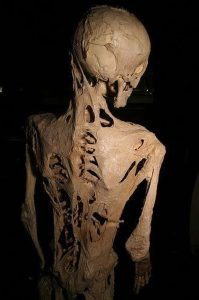

Fibrodysplasia ossificans progressiva, ochorenie kedy sú vaše svaly nahrádzané osifikátmi

Je to presne tak hrozné ako to znie. Mäkká tkanivá týchto ľudí začínajú osifikovať a metamorfovať sa na tvrdé tkanivá. Dokonca ani operácia, pri ktorej by sa tvrdé tkanivá odstránili, by nebola účinná, pretože aj hojenie by prebiehalo formou tvorby kosti.

Čo sa týka vzniku tohto ochorenia, pravdepodobne za to môže mutácia génu ACVR1. Nakoľko ide o veľmi zriedkavú poruchu (postihuje približne 1 z 2 miliónov ľudí) liečba neexistuje.